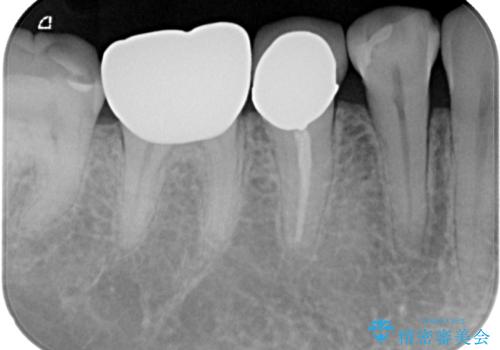

検診で見つかった齲蝕のセラミックインレー修復

- 検診で初期の齲蝕が見つかった患者様です。

これ以上神経の治療や被せものになりたくないため、初期のうちにしっかりとした治療をしたいとのことでした。

齲蝕をしっかりと除去して、精度の高いシリコーンによる型どりを行いセラミックインレーで修復しました。

唾液による接着阻害を防ぐために、ラバーダム防湿を行っています。